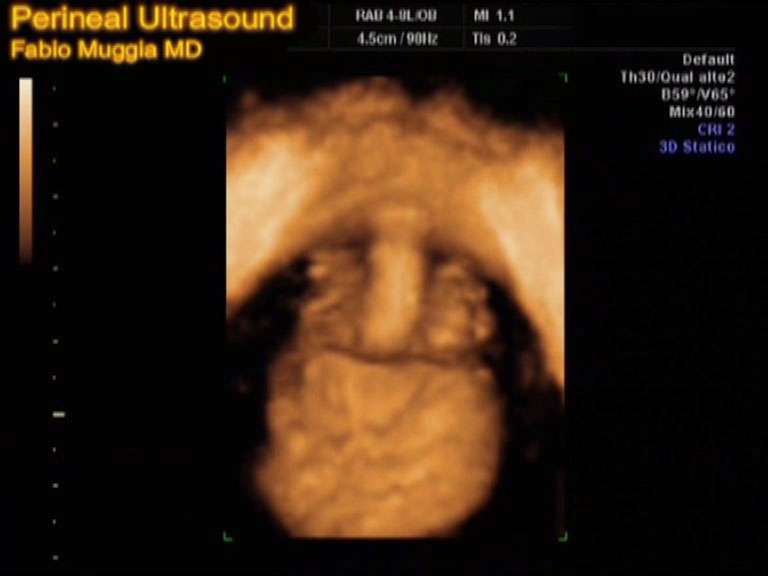

Questa indagine ecografica è innovativa perchè sfrutta la tecnologia dell'ecografia tridimensionale o 3D e tridimensionale in tempo reale, detta anche 4D, nata per la visualizzazione tridimensionale del feto nel grembo materno e per l'analisi tridimensionale dei movimenti fetali attivi. Applicando tale tecnologia in campo ginecologico, al pavimento pelvico femminile, per la prima volta si possono analizzare ecograficamente e con precisione le strutture di sostegno dell'uretra ed i movimenti che compiono gli organi pelvici, cioè l'uretra, la vescica, la vagina, l'utero, l'intestino retto ed i muscoli stessi del perineo durante i movimenti che noi chiediamo alla donna di compiere, in modo da animare i normali movimenti e il pavimento pelvico compie durante le usuali attività della vita quotidiana. Un'attenta analisi delle sequenze di immagini che vengono visualizzati sul monitor dell'apparecchio ecografico permette di capire la ragione di disturbi che una donna lamenta, consente di "vedere" davvero sia quali sono i veri difetti che determinano il prolasso, quale degli organi pelvici più degli altri tenda a scendere verso l’introito vaginale, ed anche permette di organizzare un percorso di terapia riabilitativa e chirurgica e di controllarne l'andamento durante tutte le fasi del percorso stesso. Interessante è che “l'ecografia tridimensionale del pavimento pelvico” permette a ogni donna di conoscere bene il proprio pavimento pelvico prima ancora del verificarsi dei danni, in modo tale da permettere al professionista di consigliarle un percorso riabilitativo specifico, oppure anche da sconsigliarle di sottoporsi, per esempio, ad un determinato tipo di attività sportiva particolarmente gravosa. In ogni caso l'ecografia tridimensionale del pavimento pelvico deve essere visto come uno strumento che dà alla donna una maggior consapevolezza dei rischi, delle proprie possibilità e dei propri limiti.

L'esame deve essere effettuato tramite la specifica sonda addominale volumetrica e la valutazione si avvale della tecnica bidimensionale e della modalità tridimensionale (3D), ed anche tridimensionale-real-time, o 4D. La tecnica “tridimensionale-real-time 4D” è quella che meglio di ogni altra è in grado di individuare e di dimostrare i difetti dinamici di funzionamento del pavimento pelvico che offre la possibilità di seguire visivamente i movimenti del pavimento pelvico durante le varie fasi dell'azione, come in un filmato; si possono così vedere le varie fasi del prolasso (gli “abbassamenti”) dell'utero e della vescica, i movimenti anomali dell'intestino retto, i difetti muscolari durante la contrazione volontaria, le ragioni anatomiche che stanno alla base del incontinenza urinaria; si possono persino valutare i progressi della donna sta facendo nel suo percorso di riabilitazione pelvi-perineale.